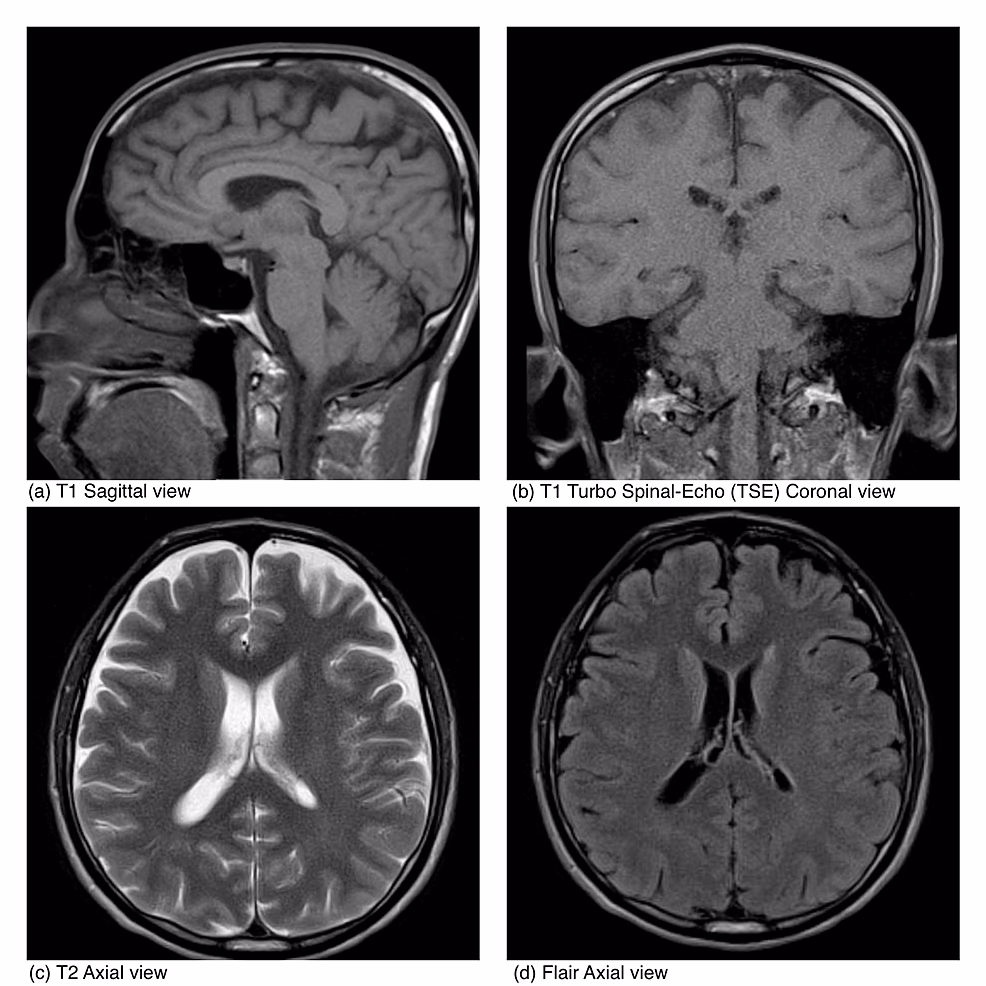

En hurtig og præcis diagnose er essentiel for en vellykket behandling. Diagnosen stilles typisk ved at analysere cerebrospinalvæsken (den væske, der omgiver hjernen og rygmarven), som udtages via en lumbalpunktur. Læger leder efter tilstedeværelsen af HHV-6 DNA ved hjælp af en meget følsom test kaldet Polymerase Chain Reaction (PCR). Magnetisk resonansbilleddannelse (MR-scanning) af hjernen kan også vise tegn på betændelse, især i områder som hippocampus, hvilket er karakteristisk for denne type encephalitis.